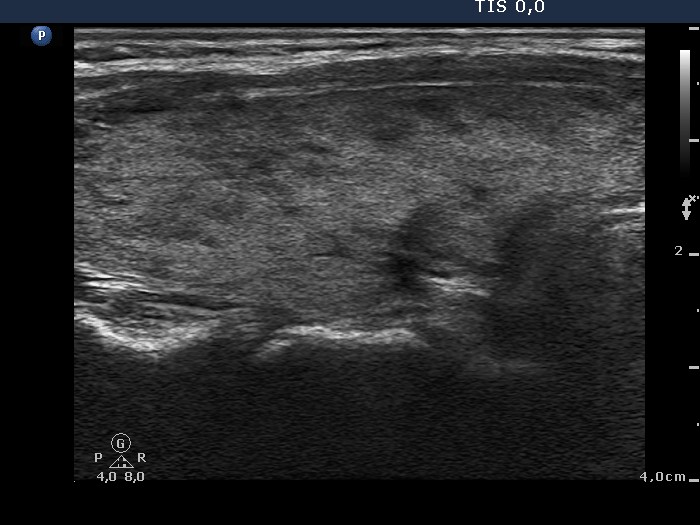

Follow-up investigation 33 months after first visit (ultrasonographic picture 2)

Patient on daily 20 mg methimazole therapy in euthyroid state

Right lobe, longitudinal scan.